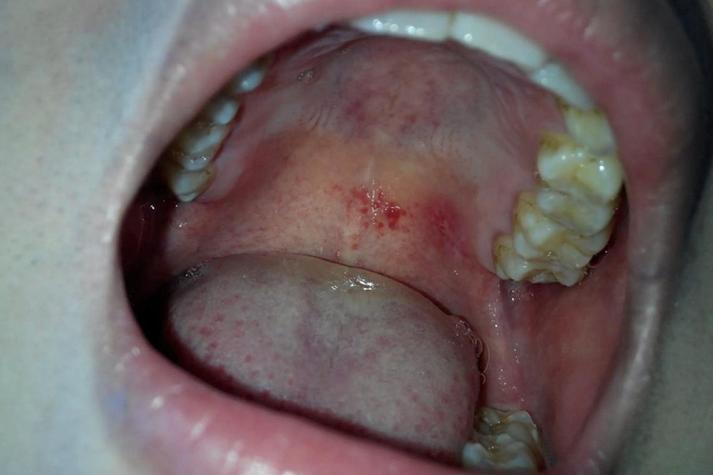

病毒感染

(图片来源网络,侵删)- 疱疹性口炎:由单纯疱疹病毒引起,初期可能在口腔任何部位(包括上颚)出现成簇的小水疱,很快会破溃形成小溃疡,伴有疼痛、灼热感和发热。

- 手足口病:多见于儿童,但成人也可能感染,除了手、脚出现皮疹外,口腔黏膜(包括上颚、舌头、颊部)也会出现小疱疹或溃疡。